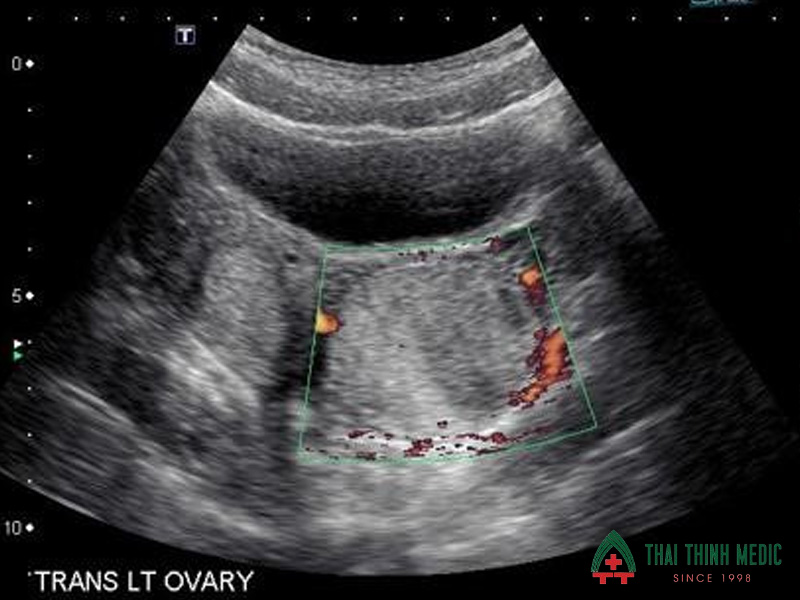

U nang buồng trứng

U nang buồng trứng là tình trạng xuất hiện các túi chứa dịch phát triển trong hoặc trên bề mặt buồng trứng. Phần lớn các u nang buồng trứng là lành tính, nhưng nếu phát triển lớn hoặc kéo dài có thể gây đau vùng bụng dưới, rối loạn kinh nguyệt và ảnh hưởng đến khả năng sinh sản.

Siêu âm phụ khoa là phương pháp phổ biến nhất để phát hiện u nang buồng trứng. Hình ảnh siêu âm giúp bác sĩ nhận biết sự xuất hiện của các nang bất thường trong buồng trứng cũng như đánh giá kích thước và đặc điểm của khối nang. Nhờ đó, bác sĩ có thể phân biệt giữa u nang sinh lý và u nang bệnh lý.

- Phát hiện các nang chứa dịch trong buồng trứng

- Đánh giá kích thước và cấu trúc của u nang

- Theo dõi sự thay đổi của u nang theo chu kỳ kinh nguyệt

- Phân biệt u nang lành tính và các khối u nghi ngờ

- Hỗ trợ quyết định theo dõi hoặc điều trị